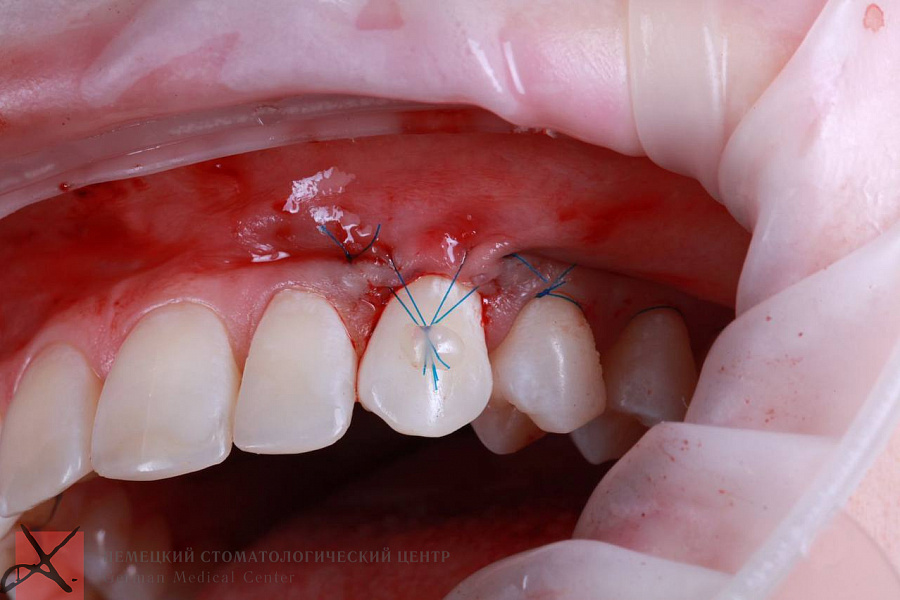

Рецессия десны

Этапы лечения

Пациенту провели рецессию десны.